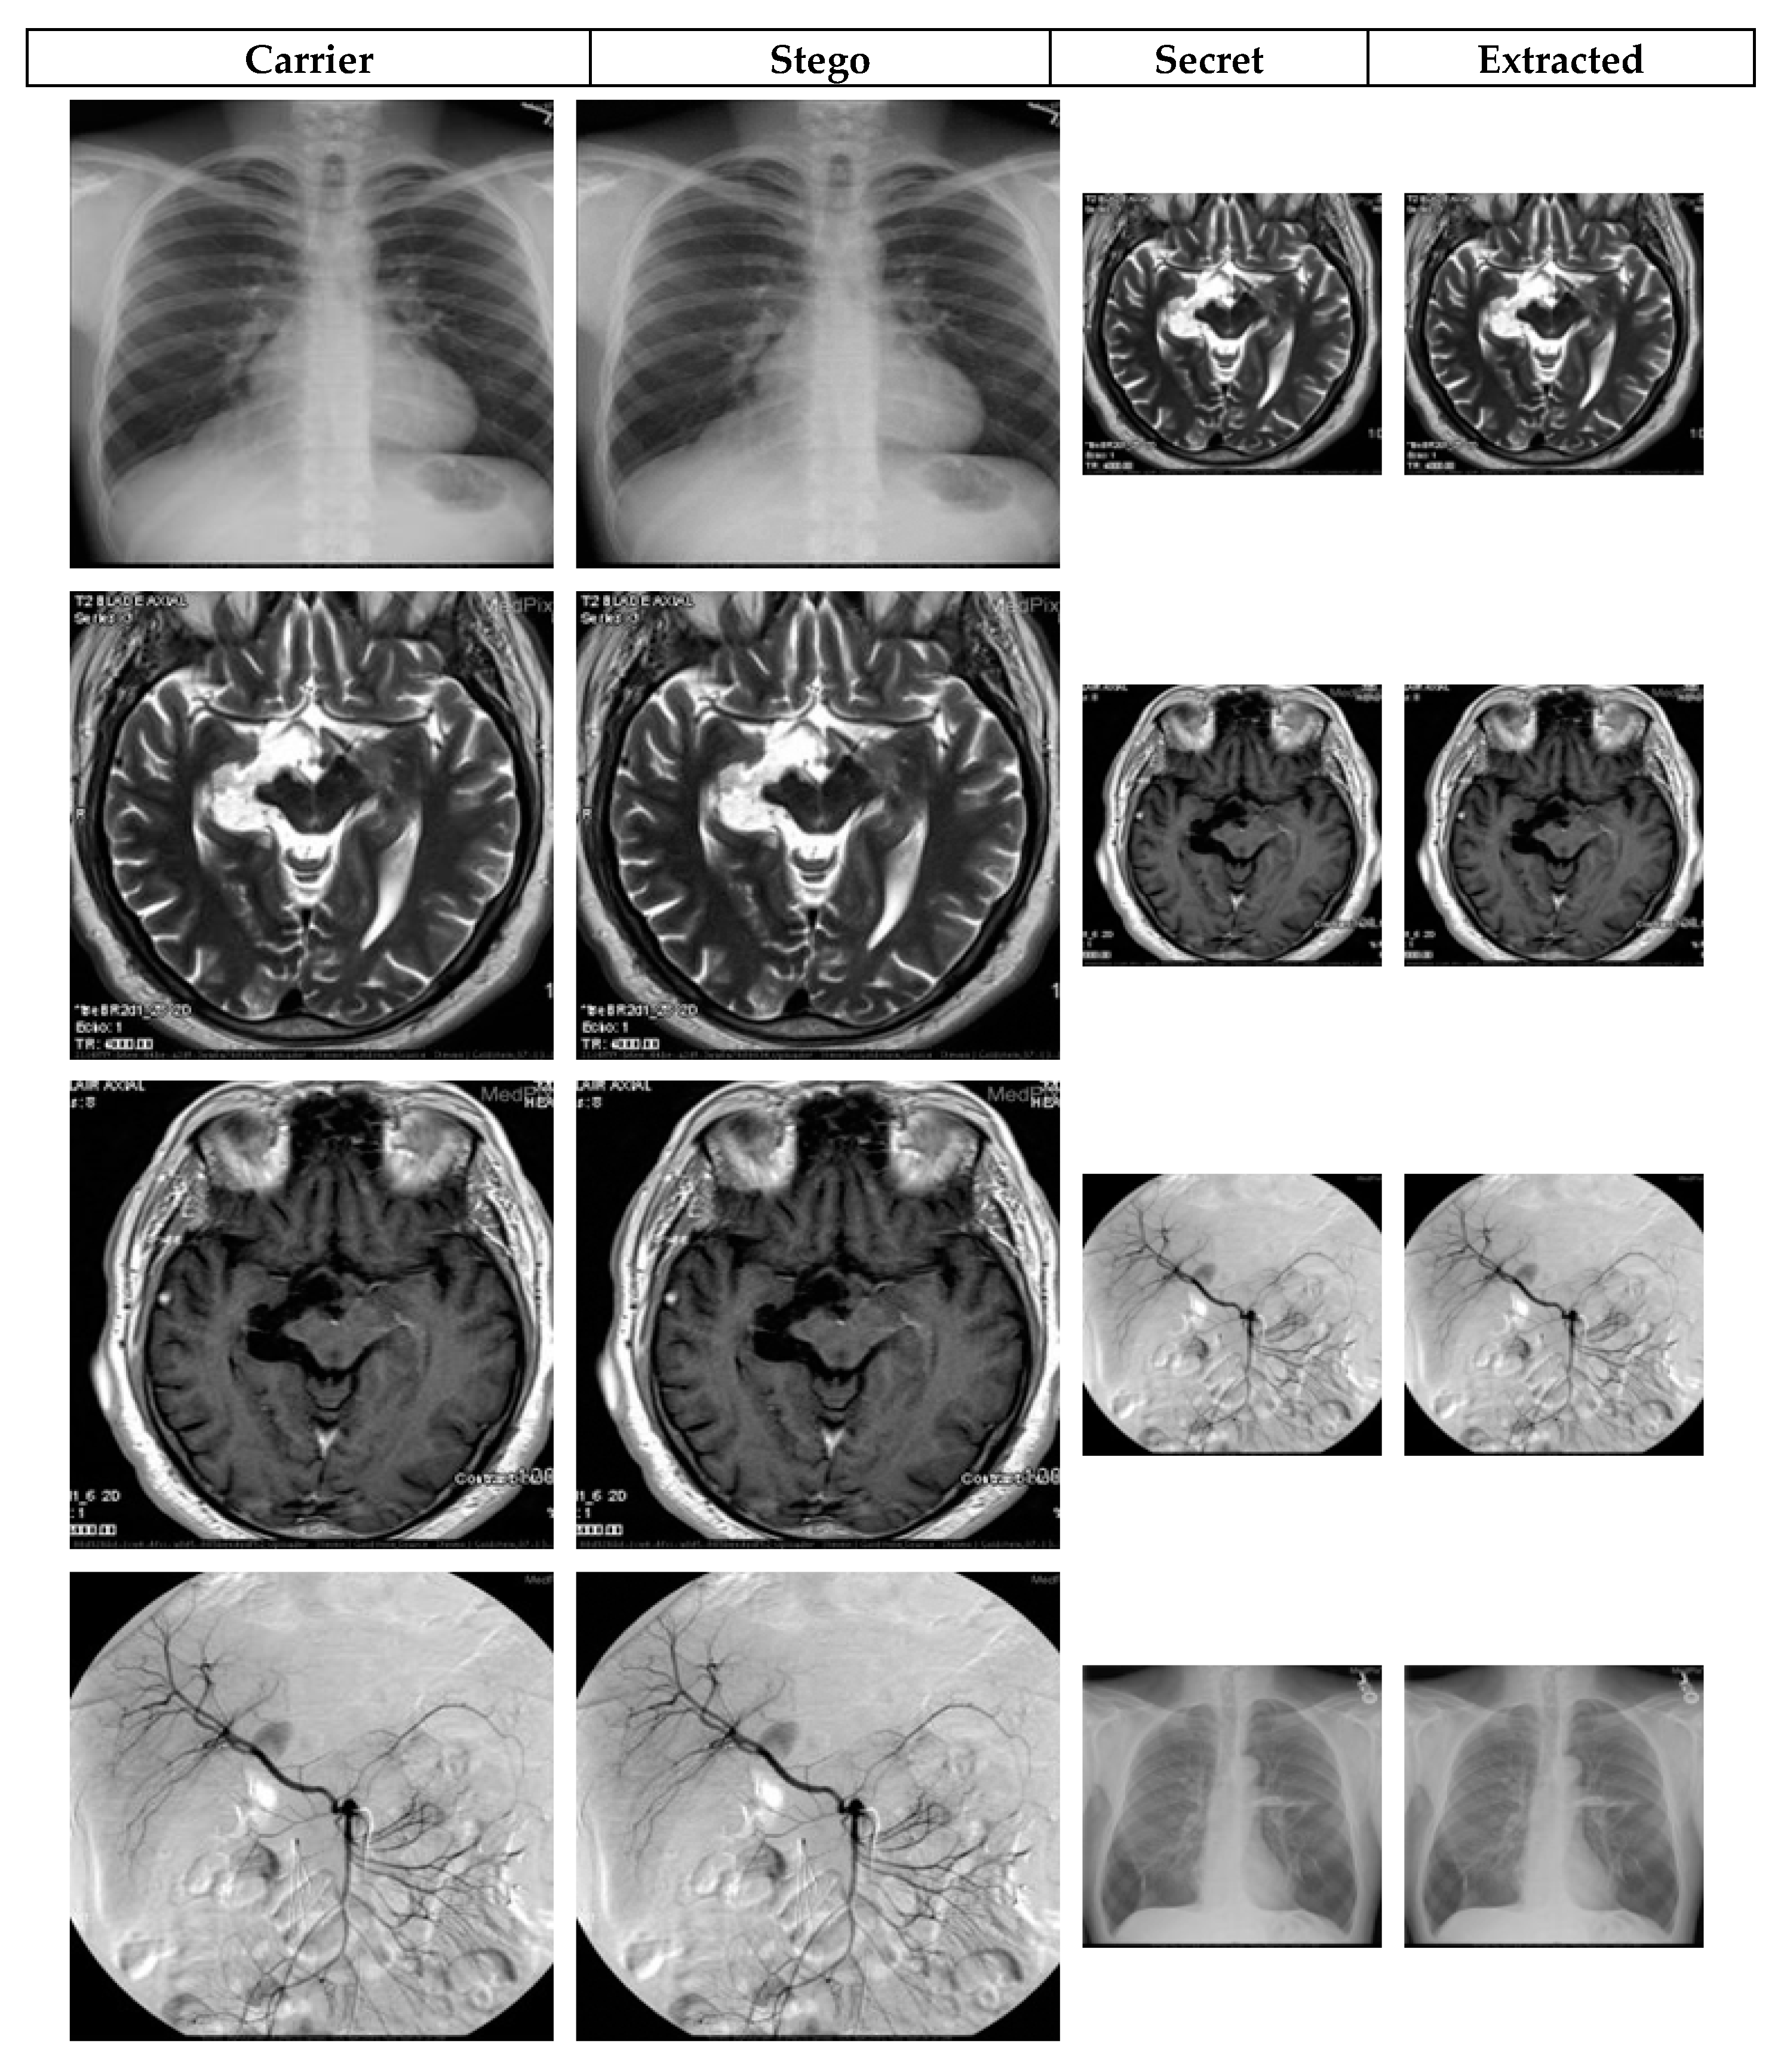

4. Simulation-Based Experiments

4.1. Image Quality Analysis